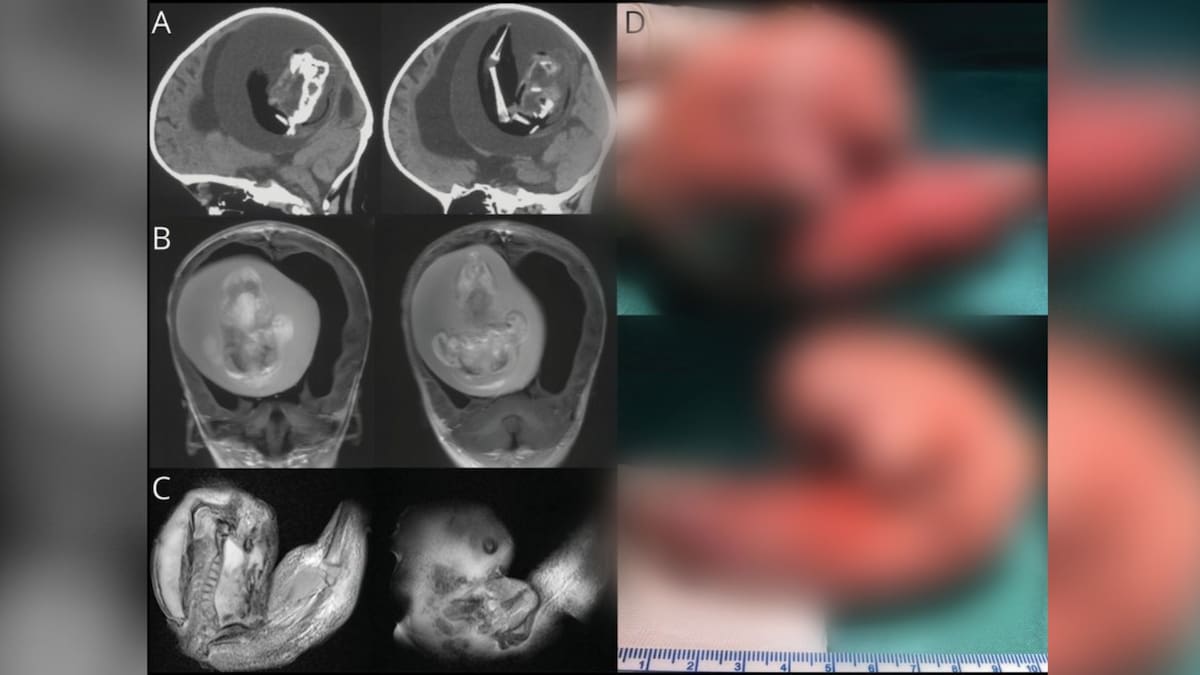

Lo que parecía ser una hidrocefalia en una pequeña de tan solo 1 año terminó siendo una sorpresa para los padres, los médicos y para el mundo entero.

Al principio y por más de un año su caso fue tratado como una hidrocefalia hasta que se logró detectar una masa extraña.